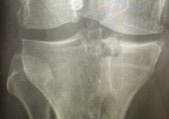

Graft sizing

Size needs to vary < 5% compared with original

Options

- X-rays accurate in 79% cases

- CT scan

- MRI accurate to within 5 mm